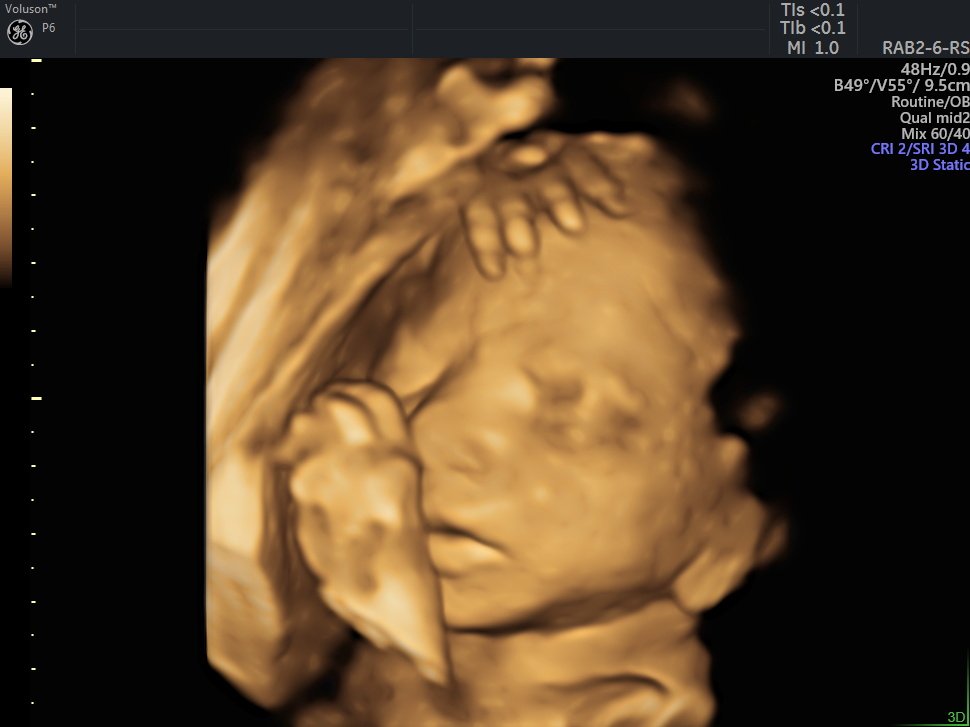

4 Boyutlu (Renkli) Ultrason ve Doppler Ultrasonografi

4 D Ultrasonografi